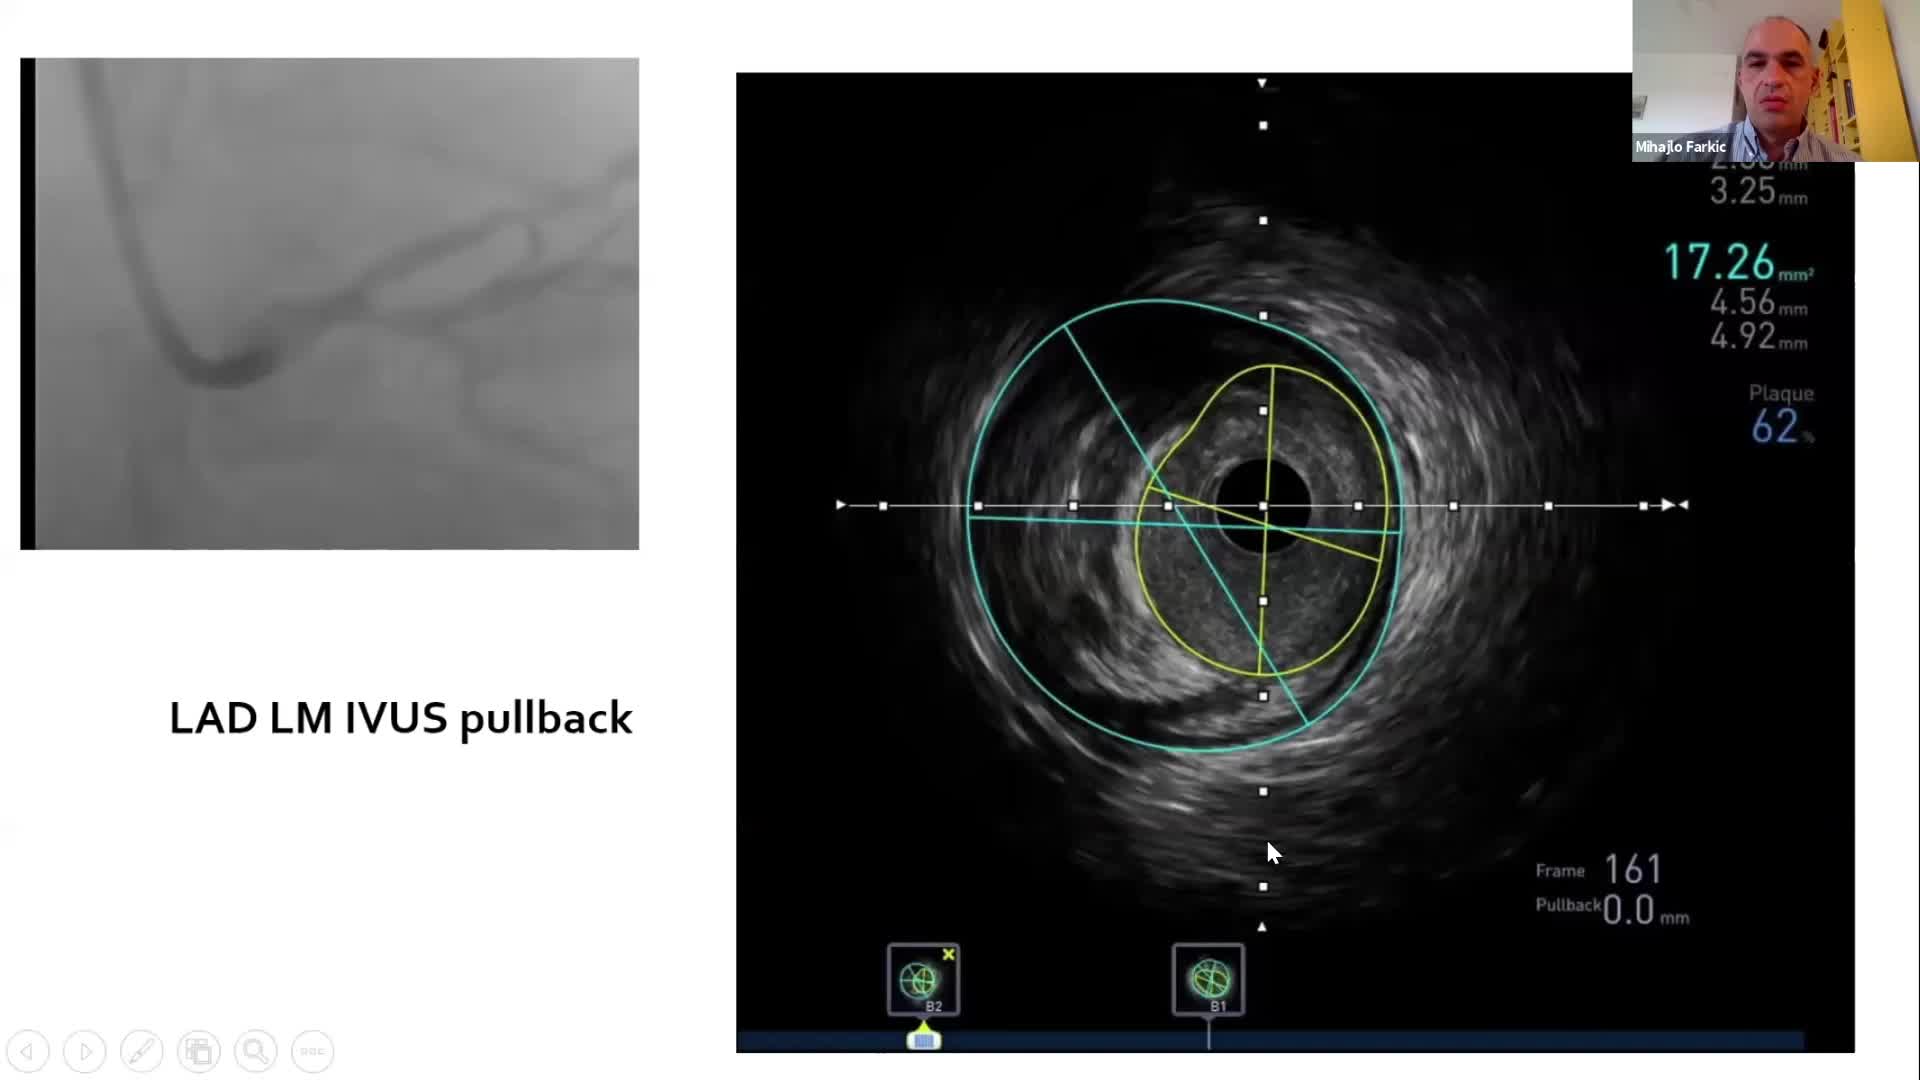

Prof Flavio Ribichini discusses the how he has implemented physiology assessment into his catheter laboratory.